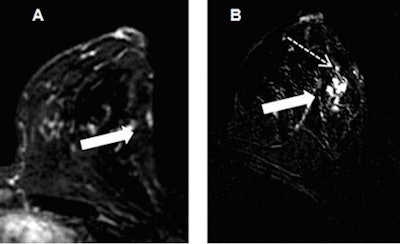

All patients were rescanned on a 1.5-tesla whole-body MRI system (Magnetom Espree, Siemens Healthcare) within 48 hours, using a standardized clinical protocol. Subtraction images were acquired at both 1.5-tesla and 7-tesla field strengths (shown below).

| Subtraction imaging of the same patient. In comparison to 1.5 tesla (A), the suspicious lesion on the lateral side of the left breast (broad arrows) shows brighter contrast enhancement at 7 tesla (B); evaluation of lesion size, margins, and morphology are improved at 7-tesla imaging, whose more explicit contrast enhancement allows the depiction of further satellite lesions (dashed arrow). |